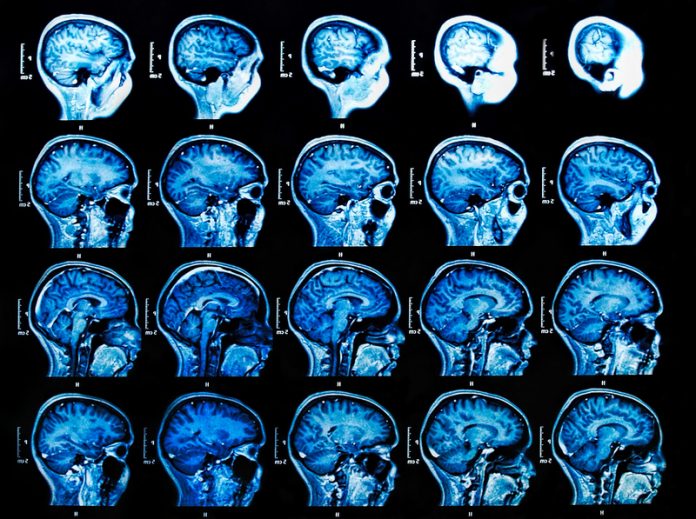

Professor Serena Carra and her collaborators are investigating the important role of small heat shock proteins in age-related neurodegenerative diseases

Most HSPs are constitutively expressed; however, HSPs are also induced upon stress to allow cells to respond and adapt, and are therefore referred to as “stress proteins”. One of the key functions of chaperones is to cooperate with degradation systems to limit the accumulation of aggregation-prone proteins, a hallmark of many age-related neurodegenerative diseases. Genetic and experimental evidence demonstrates a direct link between imbalances in proteostasis, accumulation of protein-RNA aggregates and amyotrophic lateral sclerosis (ALS), Alzheimer’s disease (AD), frontotemporal dementia (FTD), and motor neuropathies. Moreover, mutations in small HSPs and co-chaperones (BAG3) cause neuromuscular diseases.

Stress granules are ribonucleoprotein complexes induced by cells exposed to stress. While stress granules are highly dynamic in healthy cells, they become dysfunctional and less dynamic in ALS, AD and FTD, ultimately accumulating and contributing to disease. Boosting the HSPB8-BAG3-HSP70 granulostasis complex might help the cells to maintain the functionality of stress granules, thereby delaying disease progression. Carra and her collaborators are synergising their efforts to identify other players of granulostasis and discover drugs that can upregulate the HSPB8-BAG3-HSP70 complex for therapeutic use.

In parallel, the research team also identified mutations in HSP genes linked to rare neuromuscular diseases that are the object of current investigations.